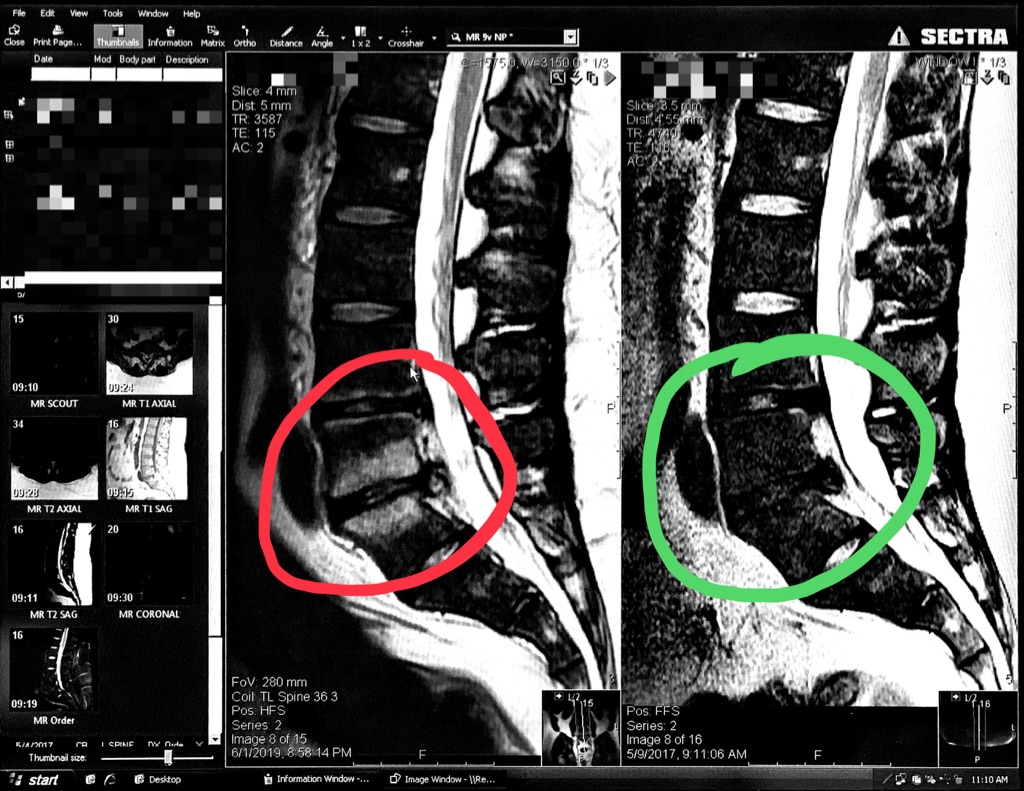

I herniated two discs in my spine back in 2008. Since then I have been in and out of doctors’ offices trying to manage it. There have been ups and downs but for the most part I learned to live with it. Things took a turn for the worse starting October 2018. I cannot describe exactly when it started but suddenly I was living a life of constant pain. Literally, I felt pain at all hours of the day - an absolutely terrible experience. Next thing I knew, I was cycling amongst nine different doctors trying to get a handle on what was wrong. I saw this image in June 2019:

The parts of my spine in the green circle are from two years ago. The discs appear dark because they are damaged and do not carry much water anymore. See the white substance in the red circle on the bone? That was the “unknown” my doctors have been working to solve for the past couple months. For the first two weeks there was a legitimate concern it was life threatening. Fortunately it was not life threatening but I was back to square one: why am I in so much constant pain?